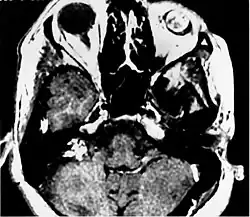

Post contrast T1 weighted MRI demonstrates intense enhancement of both the eye and the endolymphatic sac tumor in patient with VHL.

Imaging studies help to identify the tumor and the specific anatomic site of involvement. Magnetic resonance images show a hyperintensity (hypervascularity) of a heterogeneous mass by T1 weighted images. Computed tomography shows a multilocular, lytic destructive temporal bone mass, centered on the vestibular aqueduct (between internal auditory canal and sigmoid sinus).[1][6][7]